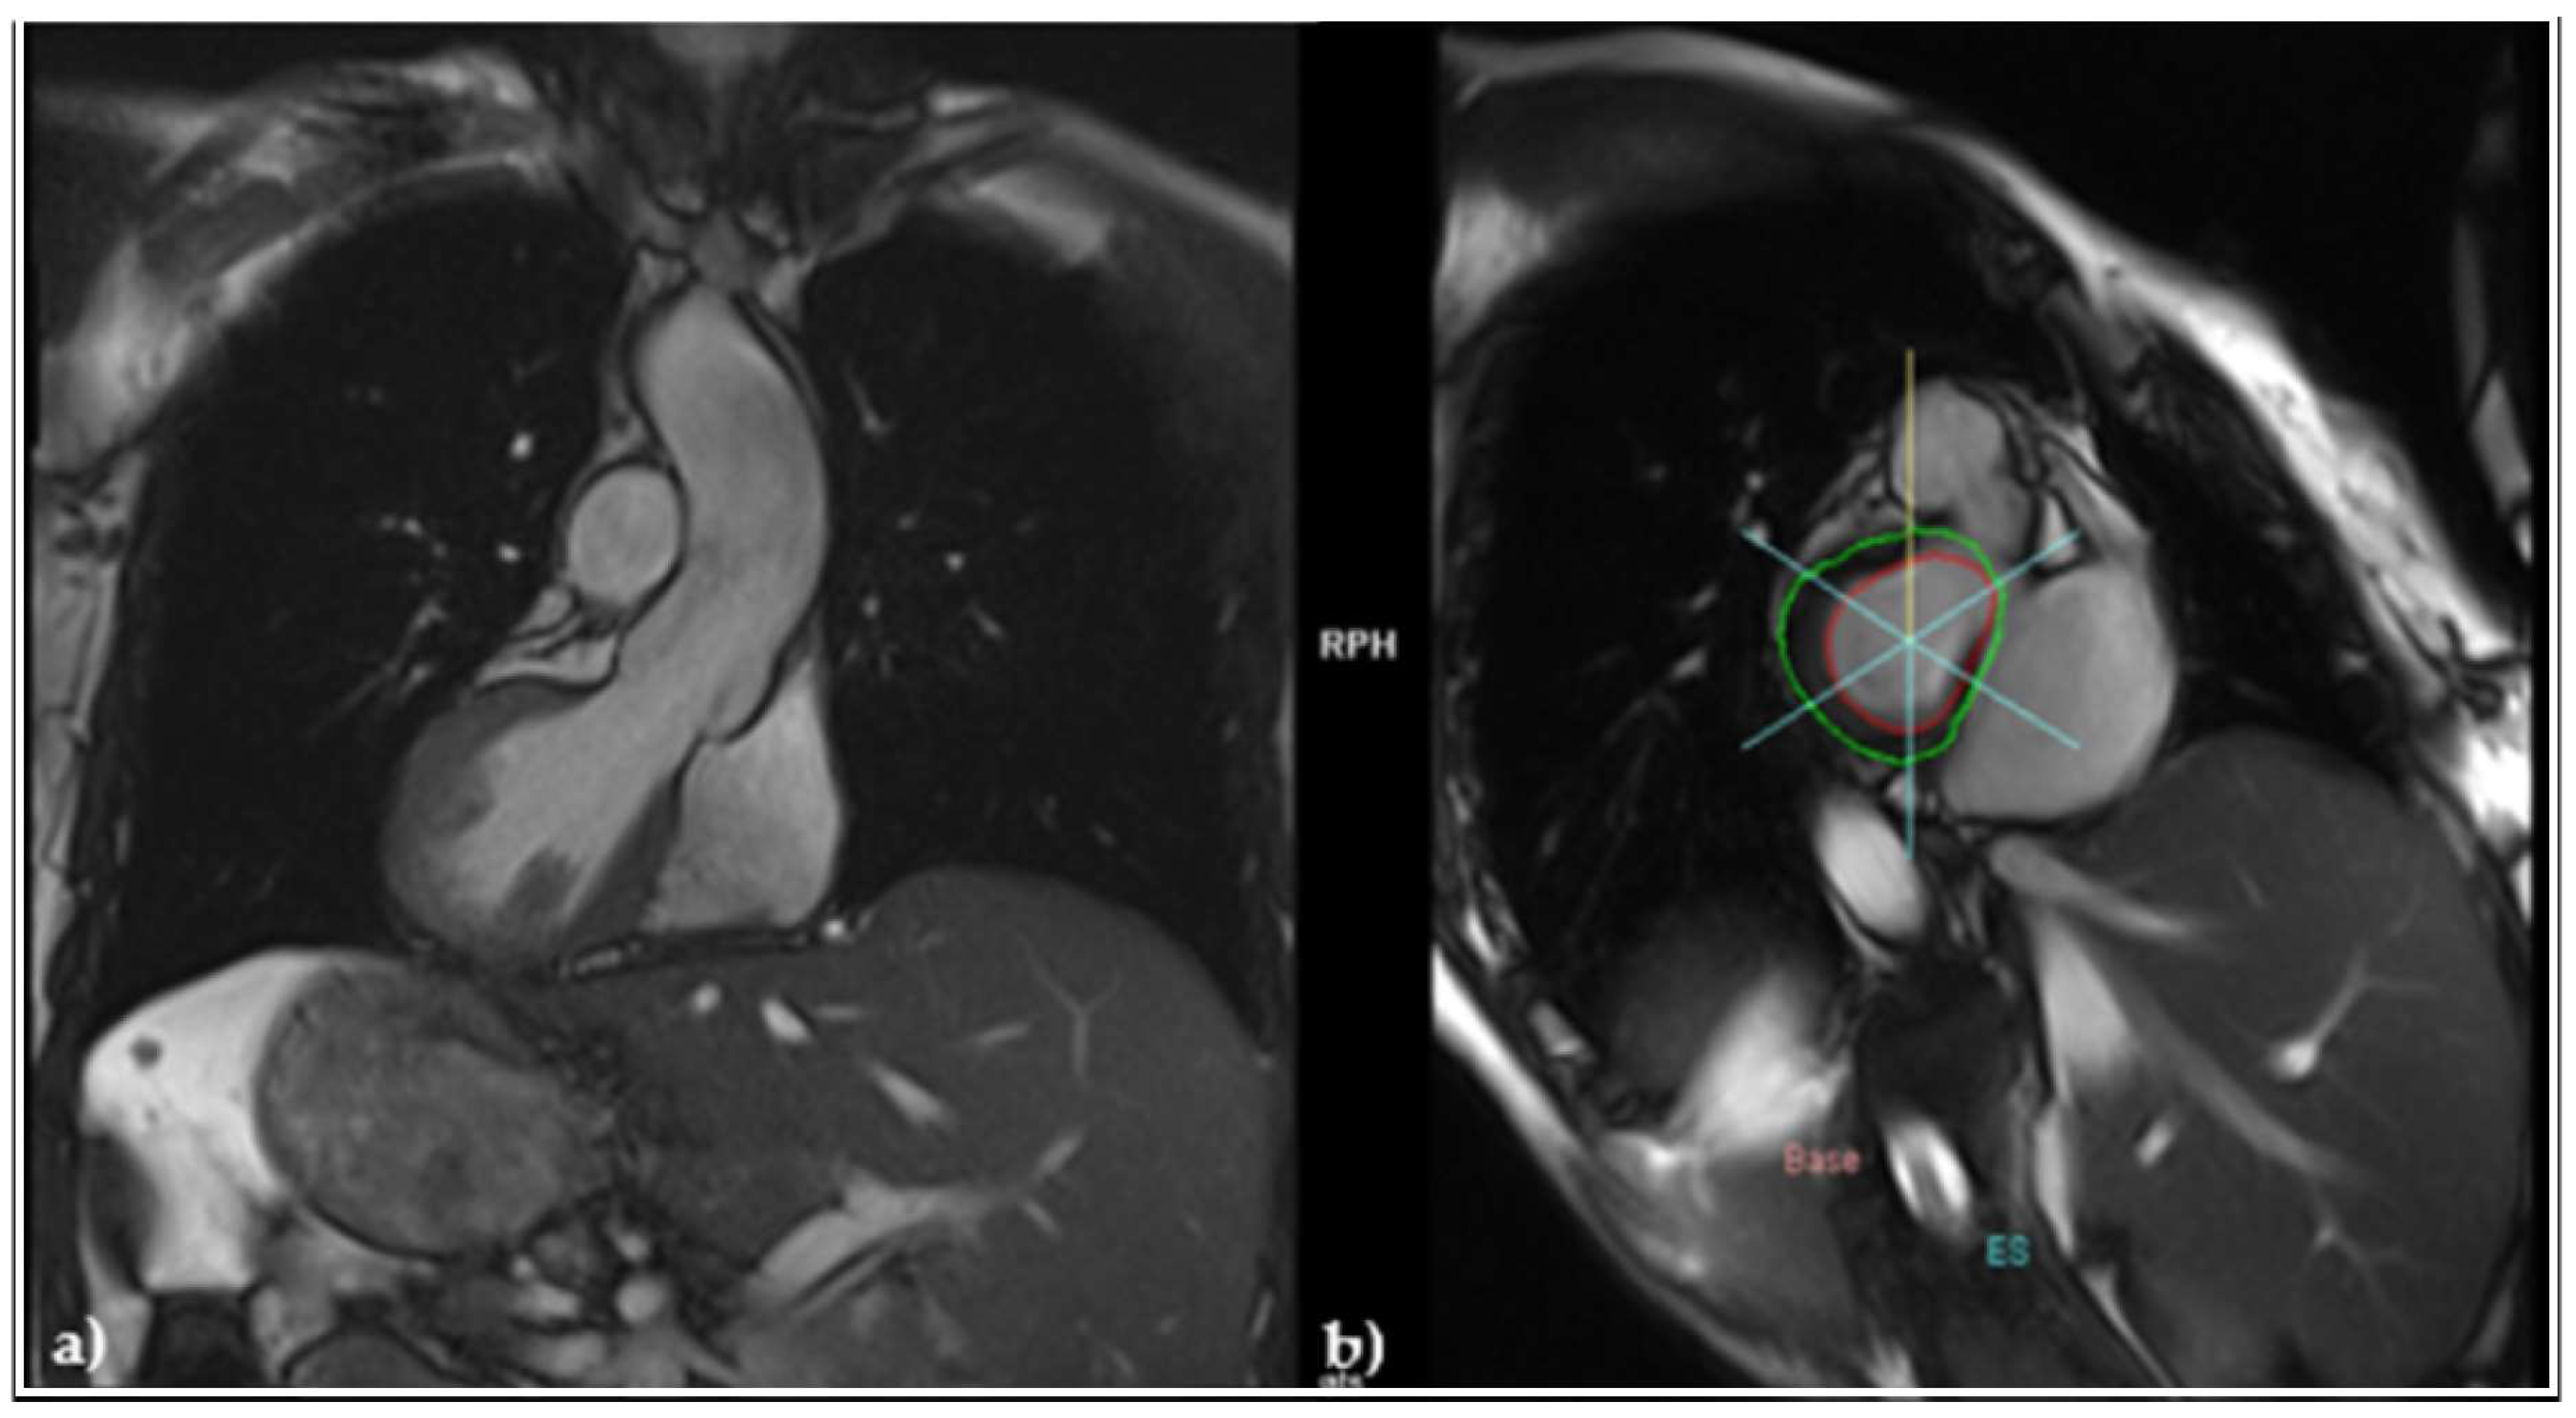

2.4. Diagnosis of Heart Failure, Initiation of Guideline-Guided Therapy, and Evolution